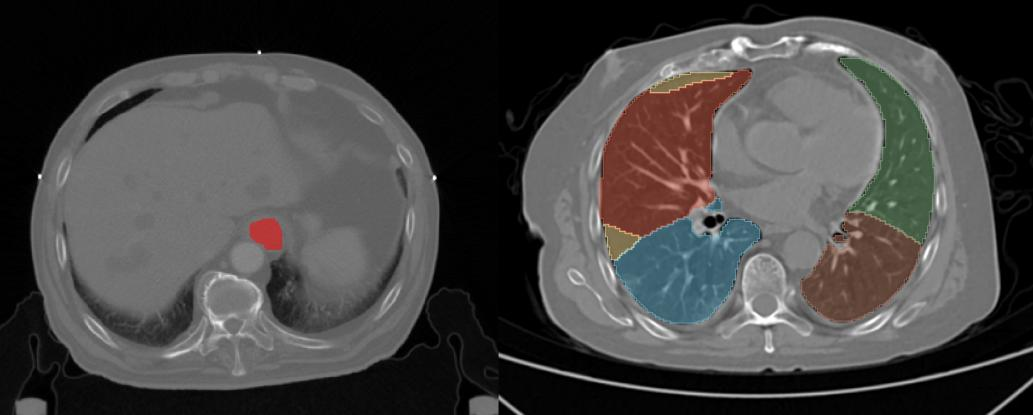

随着科研的不断深入,新的数据处理需求也不断产生。以近年来蓬勃发展的影像组学为例,为了更精确地分析DICOM等格式的影像数据,还需要对某些图像区域进行标注处理。如图13-3,要实现CT影像中器官或肿瘤部位的自动化识别,需要人工标注大量训练样本,来开展基于监督学习算法的预测。

图13-3 医学影像的分割示例(左:食管癌人工标化感兴趣区域,右:深度学习肺部影像数据分割)

在进行影像数据标注时,标注人员必须具备相应的影像学知识储备,才能够在各类图像中,准确地判断出病灶的具体位置和范围,并进行勾画,这是确保数据标注准确性和研究质量的关键,培训以及抽样检查是必不可少的步骤。